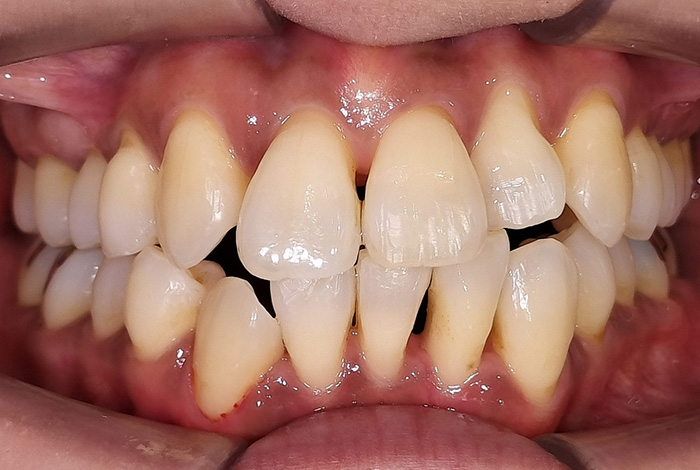

前歯の変色と摩耗による長さの不ぞろいを改善した審美治療症例

Before

【術前】:前歯の変色と歯ぎしりによる摩耗により、長さの不ぞろいがみられました。

【術後】:ジルコニアプレミアムクラウンで色調と形態を整え、自然感のある口元に改善しました。